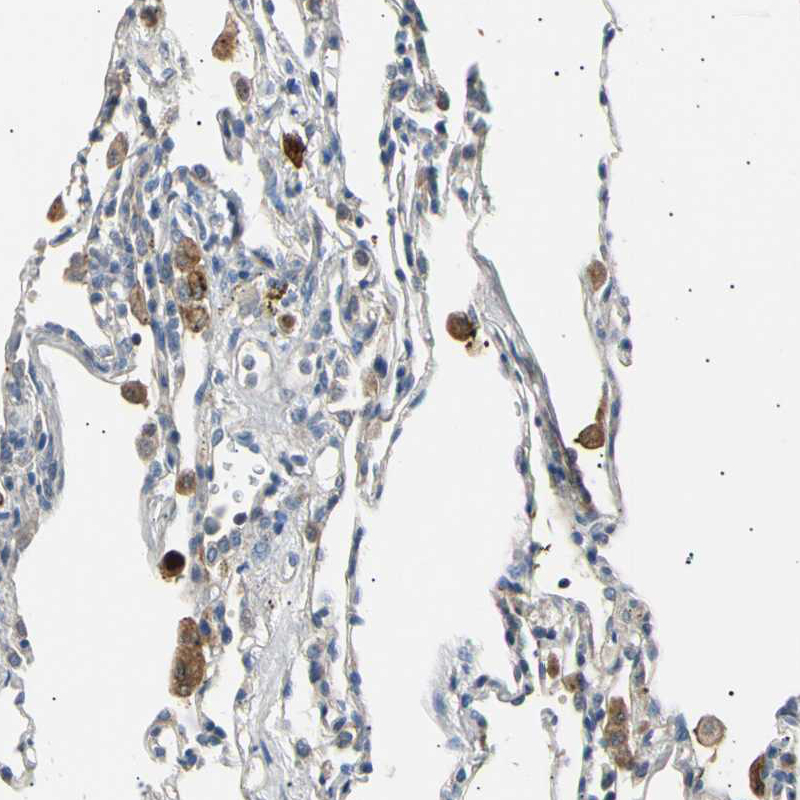

Immunohistochemical staining of human lung shows strong cytoplasmic positivity in macrophages.